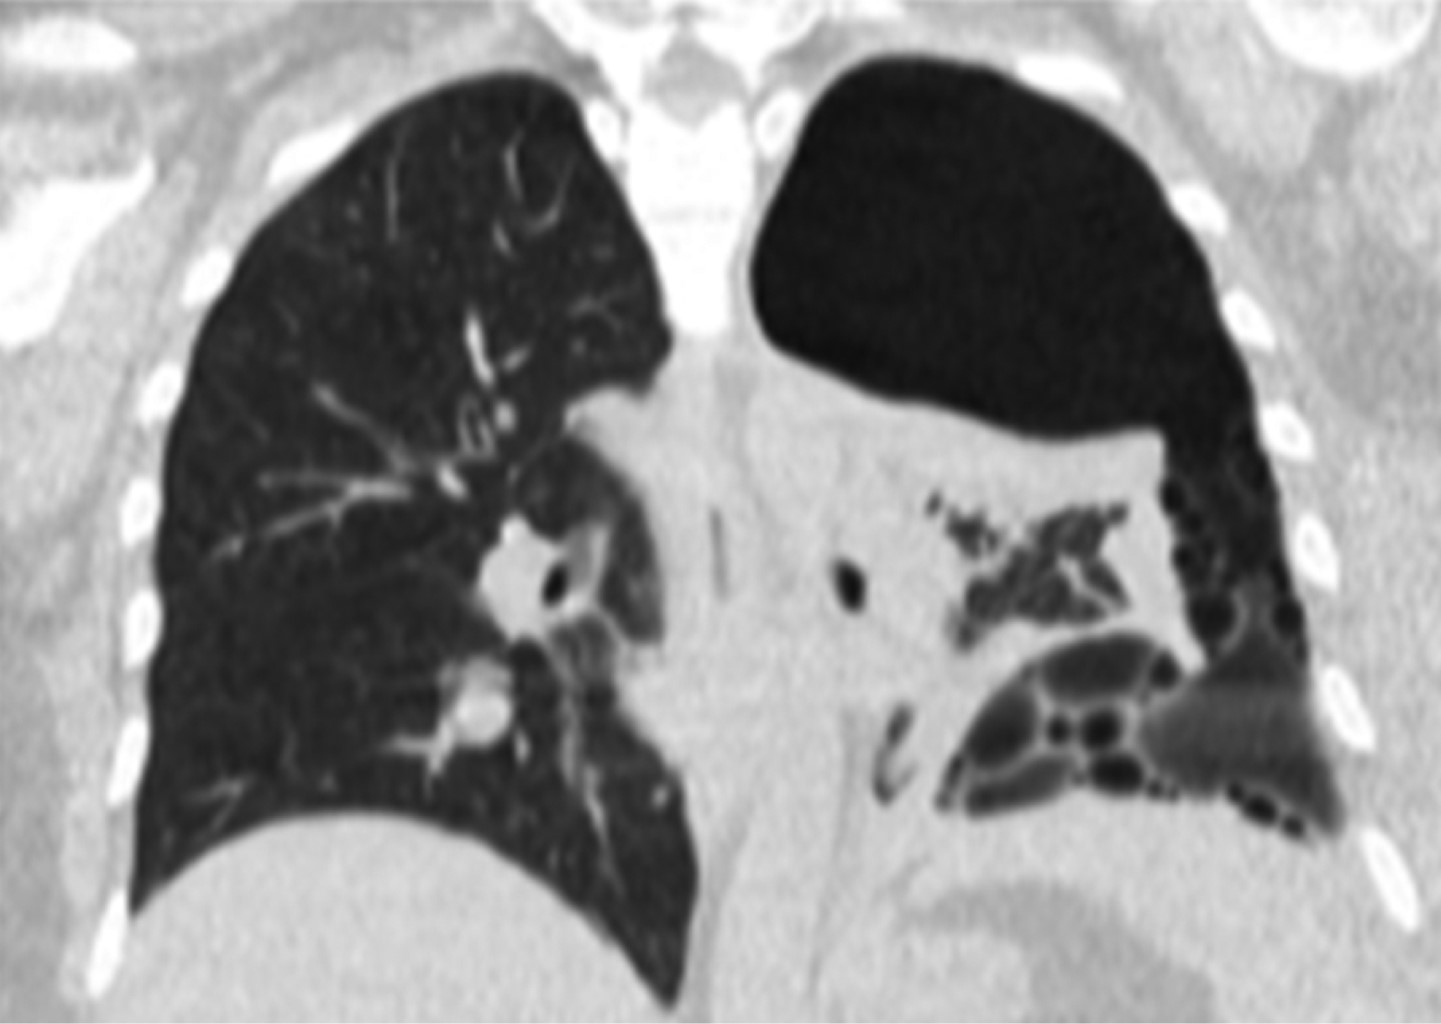

Paciente femenina de 39 años, con antecedentes de obesidad grado 3 e hipoacusia neurosensorial. Su cuadro clínico inició con odinofagia, tos con expectoración verdosa fétida en accesos, disneizante, emetizante, escalofríos, dolor en hemitórax izquierdo y leucocitosis de 34 mil a expensas de neutrófilos; la radiografía de tórax y tomografía evidenciaron un derrame pleural que comprometía todo el hemitórax izquierdo, por lo que se realizó toracocentesis donde se observó empiema por Trichomonas hominis (Figura 1), se colocó tubo endopleural y se obtuvo un total de 5,800 mL de material purulento. Se inició tratamiento antimicrobiano con metronidazol. Posterior al drenaje de líquido purulento, en tomografía de control se evidenció presencia de pulmón atrapado, loculación persistente y falta de resolución posterior a cinco días de tratamiento. Razón por la que fue enviada a cirugía de tórax.

Nuestra paciente fue tratada con metronidazol 500 mg vía intravenosa cada ocho horas, ceftriaxona 2 g vía intravenosa cada 24 horas, colocación de sonda endopleural y, por último, cirugía de tórax debido a la presencia de pulmón atrapado (Figura 2). Se realizó decorticación de lóbulo superior y adherenciólisis de lóbulo inferior en su cara anterolateral y posteroinferior. El único factor de riesgo encontrado fue la presencia de obesidad, se descartó infección por virus de la inmunodeficiencia humana (VIH) o algún estado de inmunocompromiso. La duración de la terapia antibiótica fue de tres semanas; la paciente fue dada de alta en buenas condiciones generales.

Figura 1

Figura 2